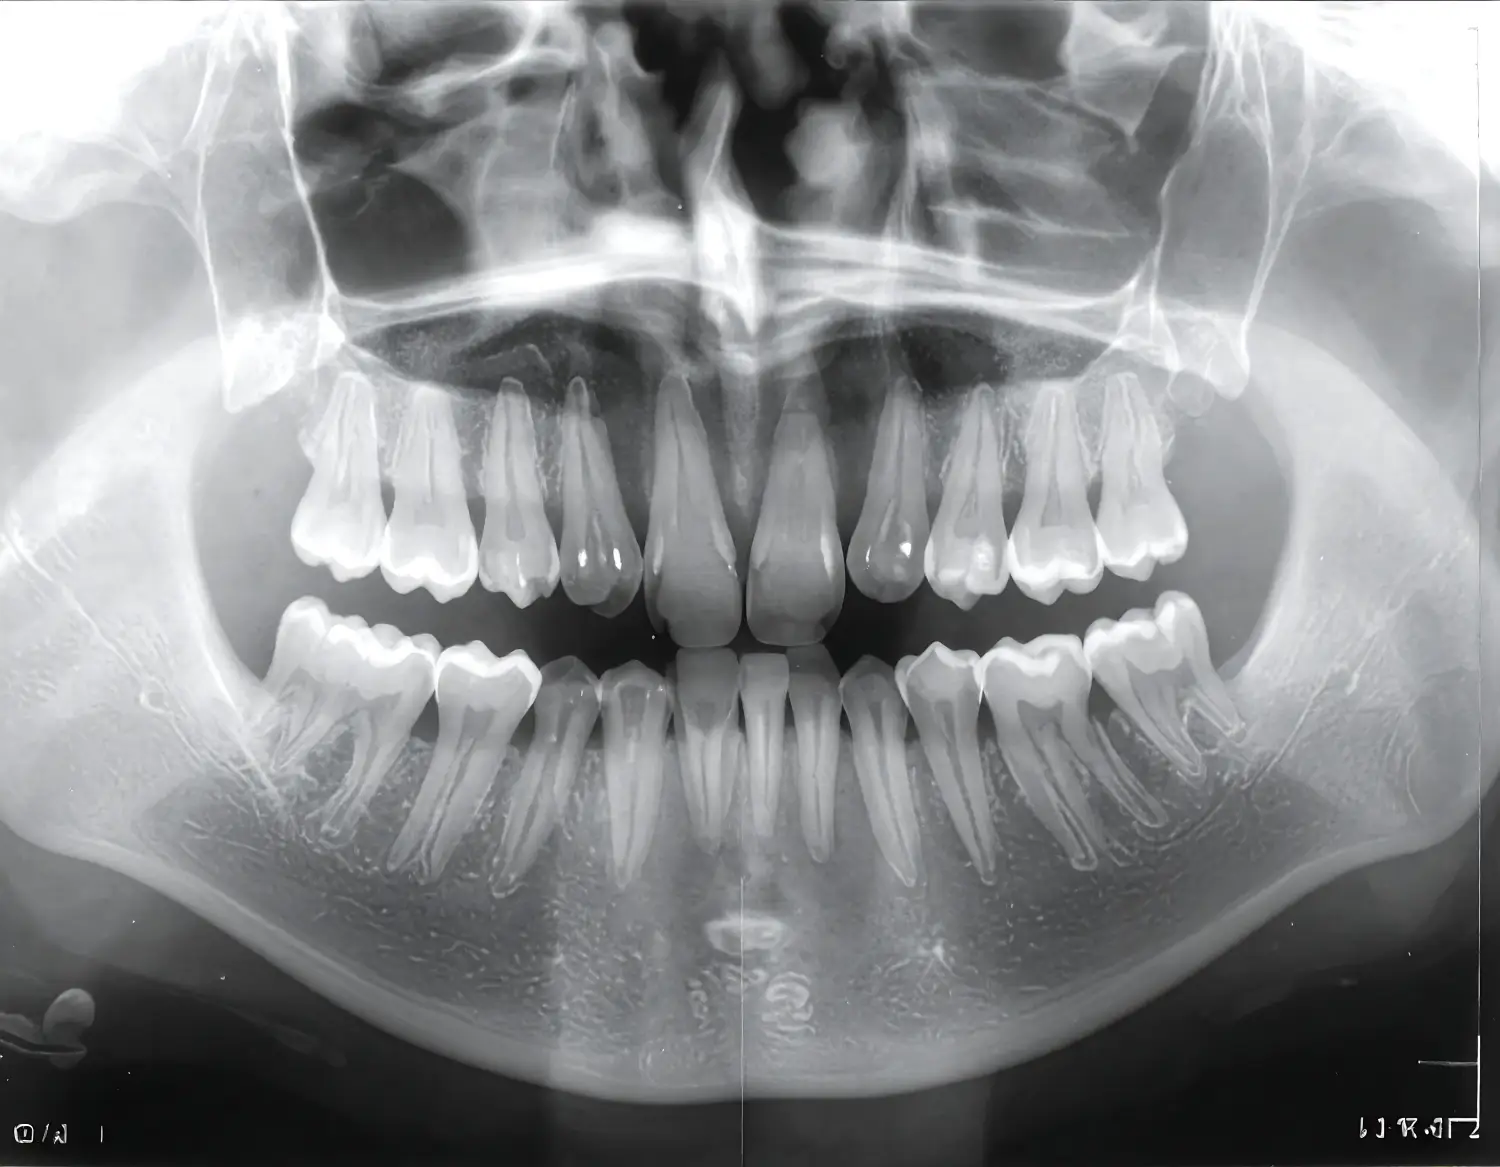

Ortopantomografía

Conocida comúnmente como radiografía panorámica, ofrece una imagen bidimensional obtenida también a través de rayos X. A diferencia del TAC, presenta menor nitidez y precisión y no es una imagen digital, ya que normalmente se entrega en formato impreso. Esta prueba resulta útil para observar la posición dental y evaluar las articulaciones y los maxilares.